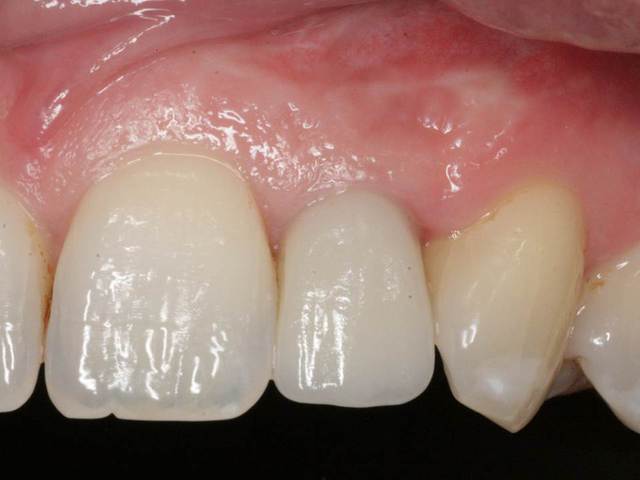

J'ai de tout en boutique..jeune homme 25 ans accident de piscine choc sur la bordure ( fêlure existante..fistule), extraction le jour même, temporisation 4 mois (avec un bout de trombone) Monobloc 16mm 60N, prep cap zircone droit 2/2 provisoire ion, temporisation 3 mois ceramo ceram..

J'ai de tout en boutique..jeune homme 25 ans accident de piscine choc sur la bordure ( fêlure existante..fistule), extraction le jour même, temporisation 4 mois (avec un bout de trombone) Monobloc 16mm 60N, prep cap zircone droit 2/2 provisoire ion, temporisation 3 mois ceramo ceram.. suite des photos :)

Ci dessous une variante avec un deux pièces ( la 2eme photo c est 24 mois après la cémentation)

Au contraire..si tu regarde attentivement les radios tu veras qu'en quelques mois il y a une néoformation osseuse autour des micros spires. On voit un manque le jour de la pose et plus d'os avec la Procera. Volontairement j'ai pas plus enfoncé l'implant ..Si j'avais ouvert j'aurai bousillé tout le potentiel cicatriciel..Charon l'a démontré depuis longtemps en paro. Aux patient je leur explique que "Ouvrir c'est comme tondre le gazon avec un motoculteur" .

Donc il y maintien et renfort du parodonte.

Si à ça tu rajoutes "l'amitié" de la gencive avec le zircone il n'y a pas de raisons de perdre quoi que ce soit..